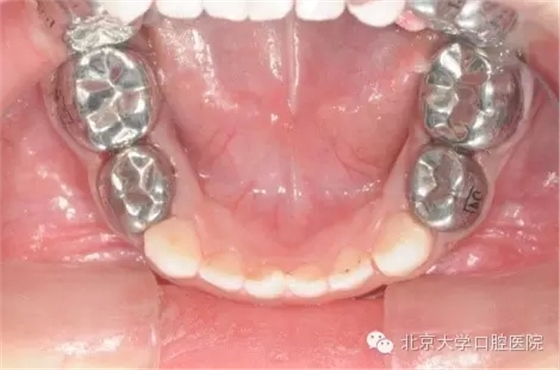

全麻治療因?qū)⒂?jì)劃進(jìn)行的所有治療集中在一次完成,而這些治療在常規(guī)門診時(shí)可能要十余次才能完成,因此牙齒治療的反應(yīng)有疊加,在全麻治療術(shù)后可能出現(xiàn)明顯的咬合不適,牙齒腫痛等情況,請(qǐng)遵醫(yī)囑進(jìn)行有針對(duì)性的處理,一般說來一段時(shí)間后這些癥狀都能消退。7為什么孩子的牙做了牙套?

全麻治療中醫(yī)生對(duì)缺損較大的后牙經(jīng)常會(huì)采用“預(yù)成冠”修復(fù)的方法,預(yù)成冠由不銹鋼制成,可以很好的恢復(fù)牙齒的外形并預(yù)防牙齒及充填體折斷,并不影響牙齒替換。